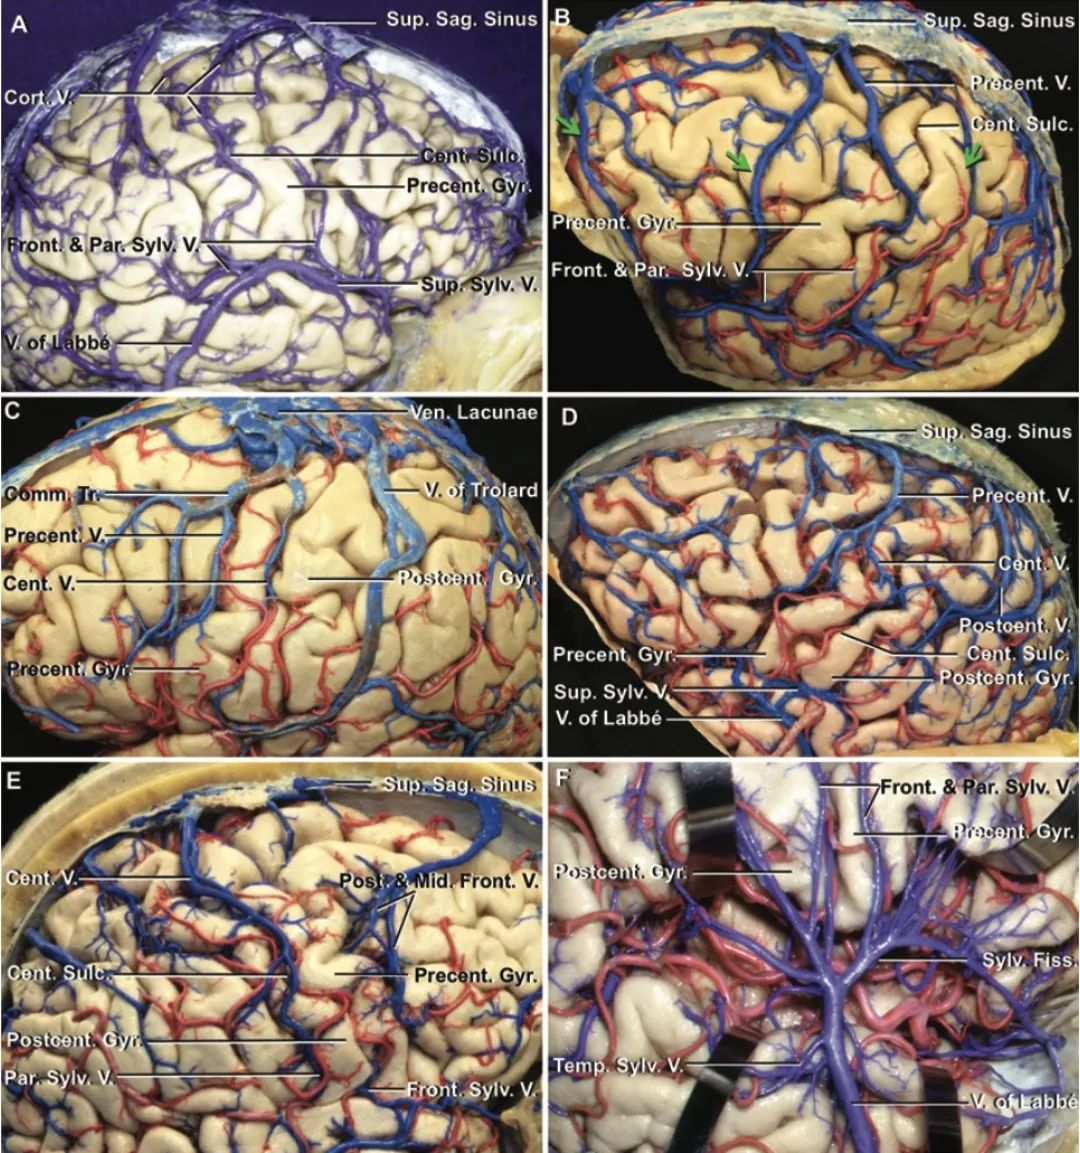

解剖-中央叶-神经(皮质-皮质下)、血管(动脉、静脉)

• 显微手术:蛛网膜下操作保留重要血管(动脉-静脉)、先切除关键部位。